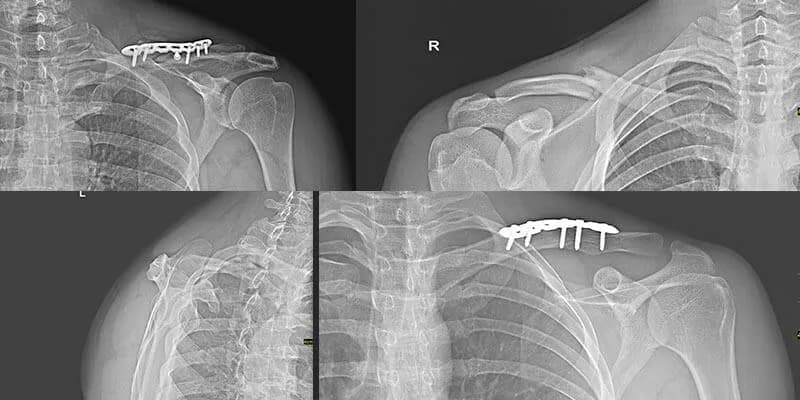

W przypadku złamań z przemieszczeniem, które często wymagają interwencji chirurgicznej, czas rehabilitacji może być dłuższy i wynosić od 6 do 12 miesięcy. Proces rehabilitacji obejmuje różne etapy, w tym ćwiczenia mające na celu zwiększenie zakresu ruchu oraz siły mięśniowej. Pacjent może rozpocząć ruchy ramieniem już kilka dni po zabiegu, a pełny zakres ruchomości można osiągnąć w ciągu 6-8 tygodni po operacji.

W przypadku złamań z przemieszczeniem, rehabilitacja jest bardziej skomplikowana i trwa od 6 do 12 miesięcy. Po operacji, pacjent może rozpocząć rehabilitację już od 3 tygodnia, a wczesne ćwiczenia są kluczowe dla uniknięcia powikłań. W tym czasie pacjent powinien skupić się na stopniowym zwiększaniu siły mięśniowej oraz poprawie zakresu ruchu, co jest niezbędne do pełnego powrotu do zdrowia.